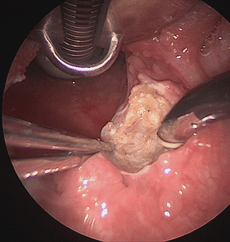

COBLATION Assisted Surgeries

A minimally invasive, low thermal technology for effective dissection and removal of tissue, COBLATION Technology has been used for ENT procedures such as tonsillectomy, turbinate reduction, laryngeal lesion debulking and soft palate.

While conventional electrosurgical devices use high temperatures to remove and cut tissue, our COBLATION Technology creates a controlled, stable plasma field to precisely remove tissue at a low relative temperature, resulting in minimal thermal damage to surrounding soft tissues. Its features include very limited depth of thermal penetration; minimal collateral tissue damage; localised effect; and controlled, volumetric tissue removal. Coblation is often preferred for its ability to reduce surgery duration and pain, minimise bleeding, and speed up recovery times in patients undergoing certain types of surgery.